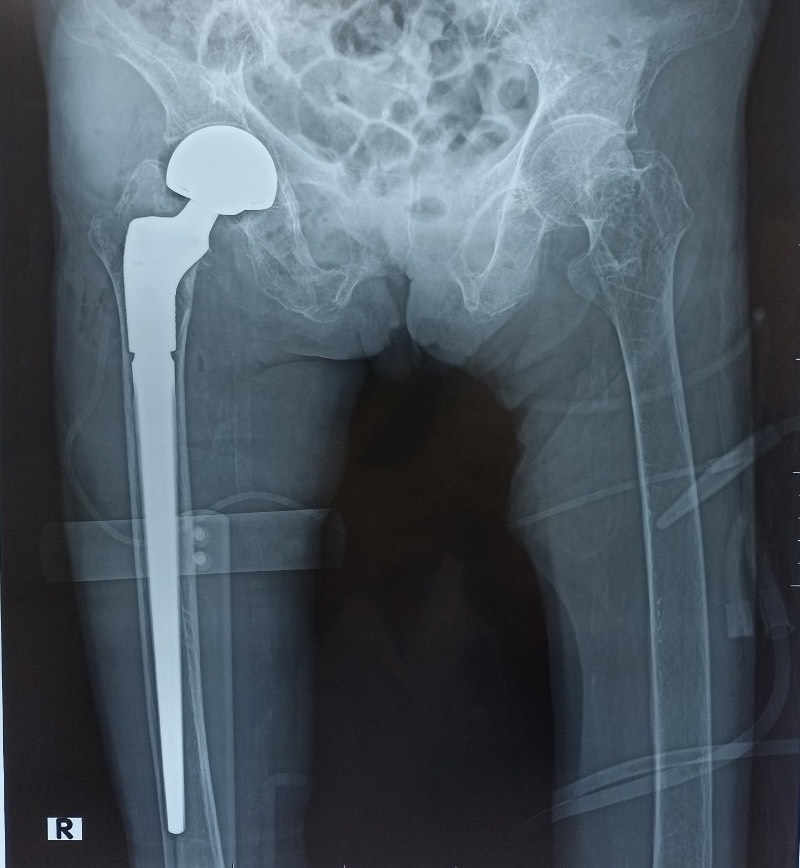

Phẫu thuật Thay khớp háng bán phần chuôi dài

Phẫu thuật thay khớp háng bán phần hay tạo hình đầu gần xương đùi một phần là một phẫu thuật chỉnh hình dùng để điều trị cho các trường hợp gãy khớp háng (cổ xương đùi, gãy liên mấu chuyển xương đùi). Trong đó, chỏm xương đùi sẽ được cắt bỏ và thay thế bằng các bộ phận có chất liệu như: kim loại, titanium, nhôm, cobalt hoặc nhựa rất cứng…

Phương pháp phẫu thuật này thường được chỉ định cho những trường hợp gãy cổ xương đùi di lệch nhiều trên bệnh nhân cao tuổi hoặc người không đảm bảo sức khỏe để thực hiện các ca mổ dài và phức tạp.

Có 03 loại phẫu thuật thay khớp háng bán phần:

- Phẫu thuật thay khớp háng bán phần chuôi ngắn không xi măng

- Phẫu thuật thay khớp háng bán phần chuôi dài không xi măng

- Phẫu thuật thay khớp háng bàn phần chuôi ngắn có xi măng

- Phẫu thuật thay khớp háng bán phần chuôi dài có xi măng